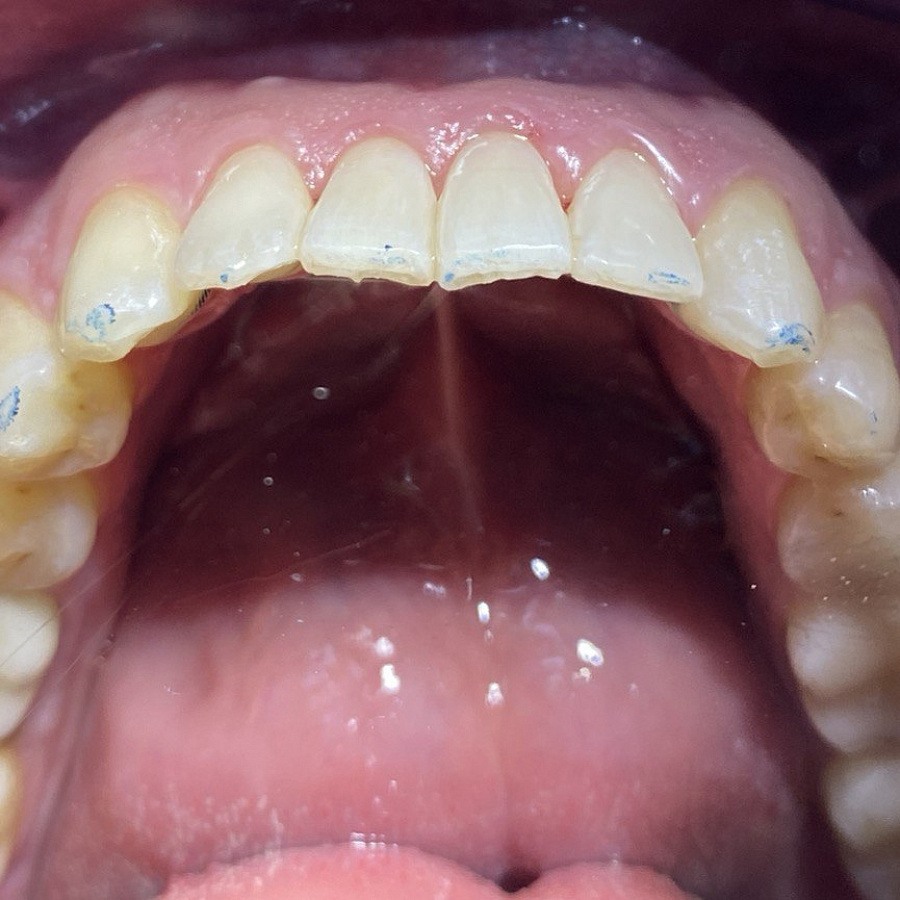

Этапы лечения

1. санация полости рта

2. ортодонтическое лечение с помощью элайнеров

3. восстановление плотных межзубных контактов с помощью ортопедических конструкций

4. виниры 12, 22 для удлинения резцов.

Ортодонтическое лечение с помощью элайнеров длилось 10 месяцев. Далее последовало протезирование и установка виниров.